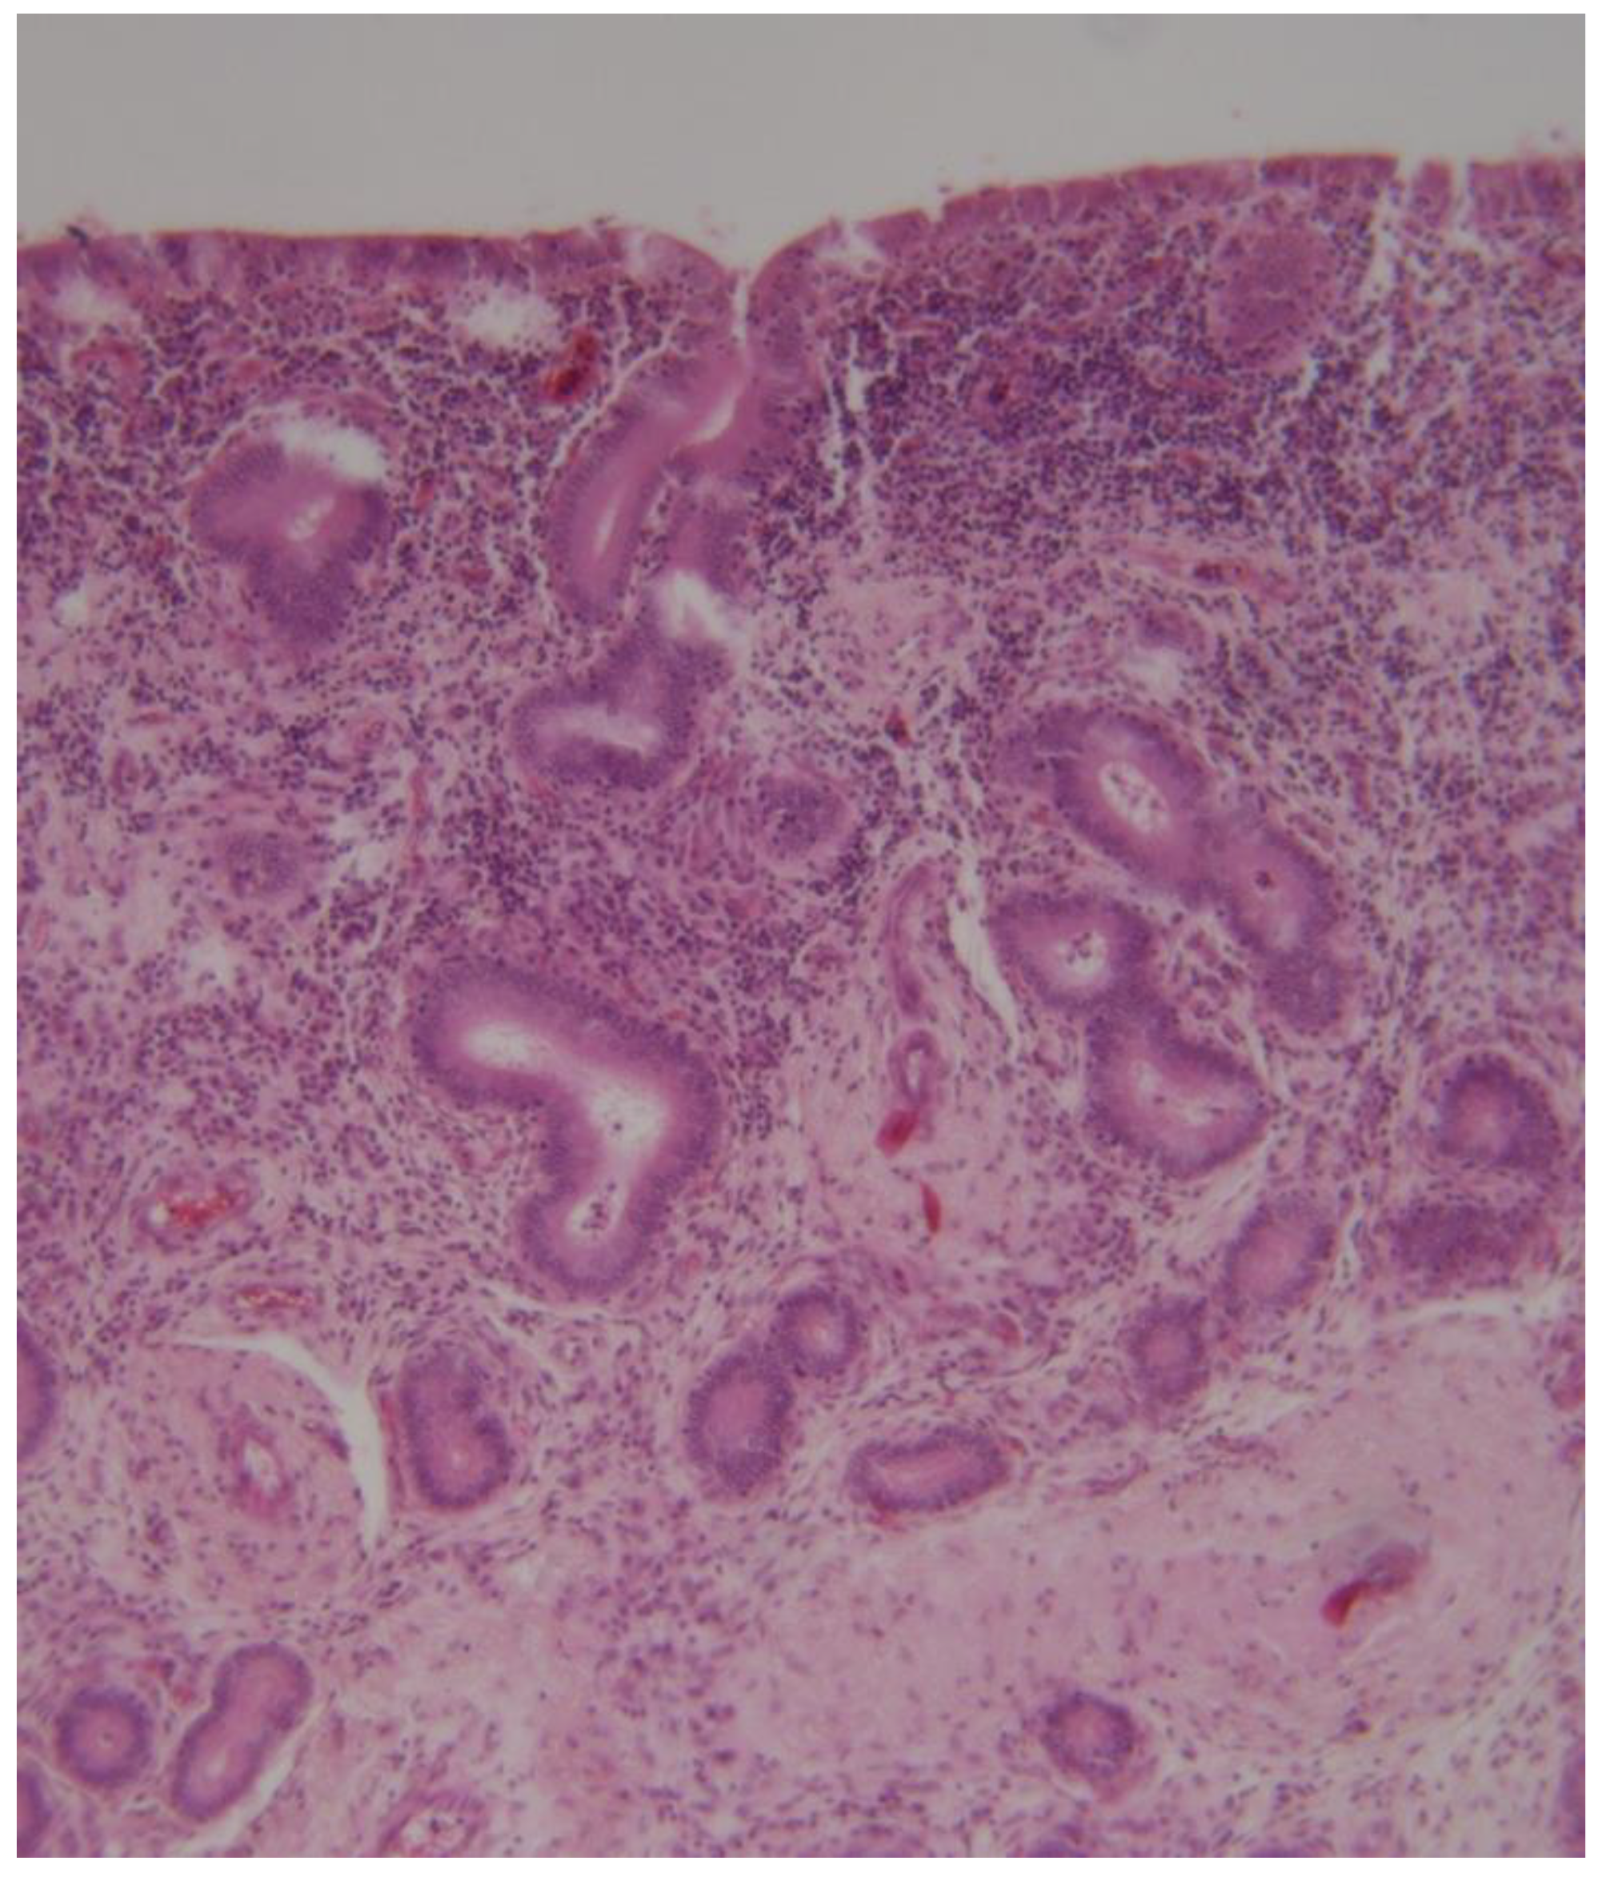

In chronic endometritis, the infiltration consists predominantly of lymphocytes, and occasional plasmacytes, macrophages, eosinophils, or mast cells (Figure 11).

A granulomatous chronic endometritis has been described in camels. Similar lesions have been described in cattle with campylobacteriosis, tuberculosis, or chronic fungal infections (Figure 12) [44,52,77,82].

Figure 11. Camel endometrial biopsy exhibiting mixed inflammation in the stratum compactum and periglandular fibrosis with cystic dilation (chronic endometritis).

Figure 12. Camel endometrial biopsy exhibiting chronic granulomatous endometritis (scale bar: 100 μm).